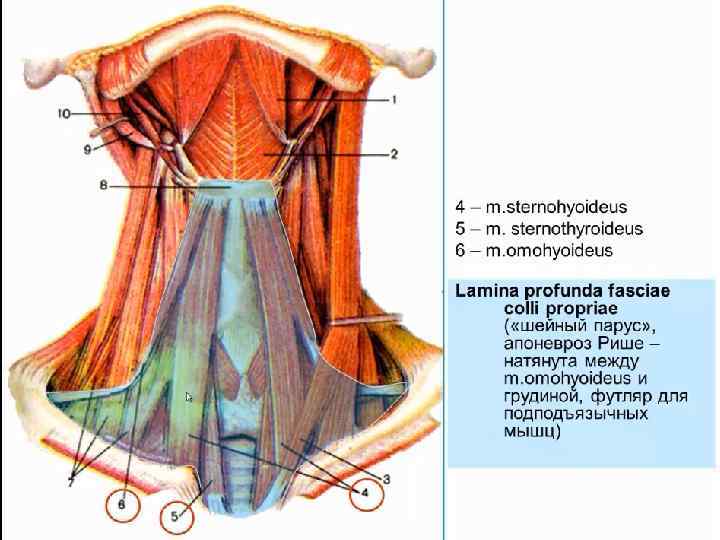

• Техника. Больного укладывают на спину с подложенным под плечи валиком, голову запрокидывают и поворачивают вправо. Разрез кожи по переднему краю грудино-ключичнососцевидной мышцы от вырезки грудины до уровня верхнего края щитовидного хряща. Послойно рассекают кожу, подкожную клетчатку, поверхностную фасцию шеи, подкожную мышцу шеи, влагалище грудино-ключично-сосцевидной мышцы вскрывают вблизи переднего края, мышцу оттягивают крючком Фарабефа латерально. Рассекают внутреннюю пластинку грудино-ключично -сосцевидной мышцы и лопаточно-ключичную фасцию шеи.

• Техника. Больного укладывают на спину с подложенным под плечи валиком, голову запрокидывают и поворачивают вправо. Разрез кожи по переднему краю грудино-ключичнососцевидной мышцы от вырезки грудины до уровня верхнего края щитовидного хряща. Послойно рассекают кожу, подкожную клетчатку, поверхностную фасцию шеи, подкожную мышцу шеи, влагалище грудино-ключично-сосцевидной мышцы вскрывают вблизи переднего края, мышцу оттягивают крючком Фарабефа латерально. Рассекают внутреннюю пластинку грудино-ключично -сосцевидной мышцы и лопаточно-ключичную фасцию шеи.

• Левую долю щитовидной железы вместе с трахеей и мышцами (грудино-подъязычной, грудинощитовидной) оттягивают и отодвигают кверху и вправо. Перевязывают нижнюю щитовидную артерию, отодвигают кверху лопаточно-подъязычную мышцу (при короткой шее её пересекают). Разъдиняют тупым способом листок внутришейной фасции, обнажают клетчатку пищеводно-трахейной борозды, где проходит левый возвратный гортанный нерв. Стенку пищевода определяют по красному цвету и продольной исчерченности.

• Левую долю щитовидной железы вместе с трахеей и мышцами (грудино-подъязычной, грудинощитовидной) оттягивают и отодвигают кверху и вправо. Перевязывают нижнюю щитовидную артерию, отодвигают кверху лопаточно-подъязычную мышцу (при короткой шее её пересекают). Разъдиняют тупым способом листок внутришейной фасции, обнажают клетчатку пищеводно-трахейной борозды, где проходит левый возвратный гортанный нерв. Стенку пищевода определяют по красному цвету и продольной исчерченности.